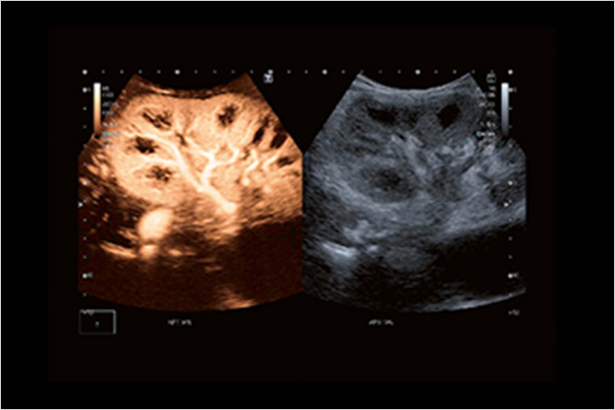

SMI帶來精細和清晰的彩色多普勒血流成像。SMI擴展了可見血流的范圍。低速微血流,SMI可以呈現(xiàn)。

CEUS非線性超聲造影成像可以讓您在廣泛的臨床應用,包括一系列的特殊檢查中獲得灌注的動態(tài)信息。